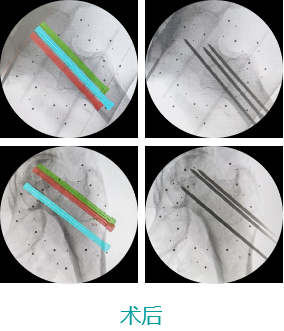

天玑II 辅助股骨颈骨折复位内牢靠术

机械人辅助优势:天玑II设置C臂跟踪器,,,,,,配准历程无需标定尺,,,,,,优化手术流程,,,,,,显著提高效率

病例泉源:北京积水潭医院